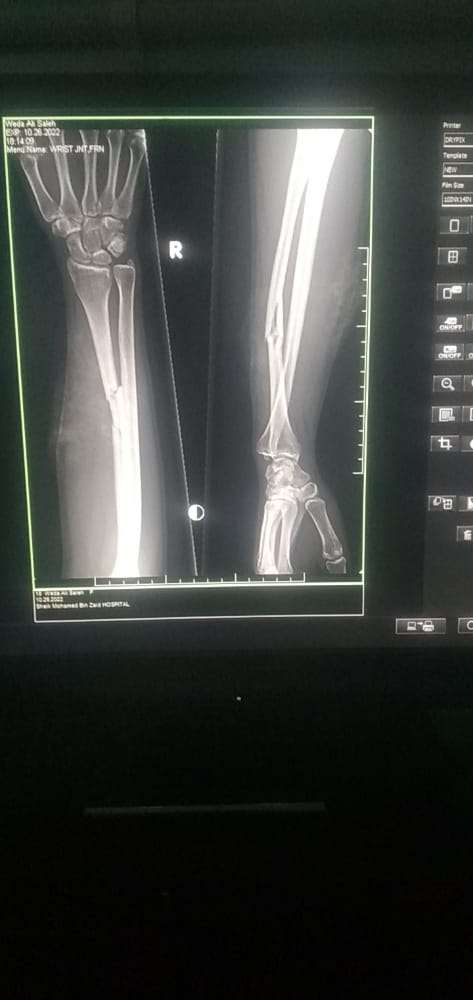

وأكد الدكتور سميح حزام مدير مستشفى زايد الميداني بمنطقة سناح في تصريح لـ “درع الجنوب” و”المركز الإعلامي لمحور الضالع” إن المستشفى استقبلت الفتاة عند الساعة السابعة مساء هذه الليلة وهي تعاني من اصابة في اليد والفخذ جراء طلقتين من قناص حوثي، وتم الكشف عن وجود كسور في عظمة اليد وأعلى الورك ولاتزال ترقد في العناية المركزة.

من جانبه, أشار مصدر عسكري أن قناصاً حوثياً، أطلق الرصاص على الفتاة (وداء محمد صالح البسيسي) 20 عاماً أثناء تواجدها في منزلها بقرية سليم غرب مديرية قعطبة.